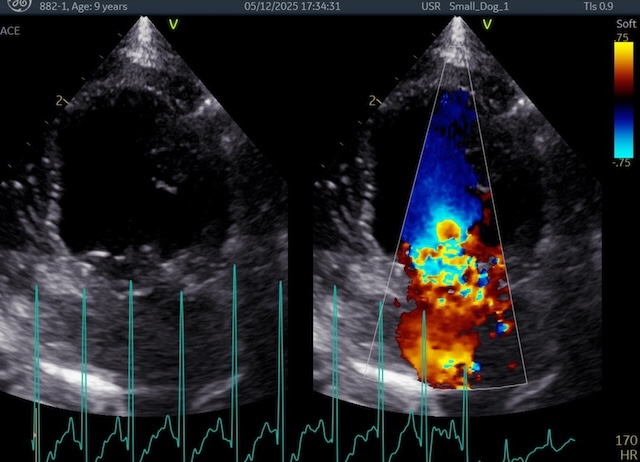

症例の術前所見は、僧帽弁の重度の逸脱があり、僧帽弁逆流量も多く、左心房の拡大および、左心室の拡大が酷かったのですが、

術前の所見↓